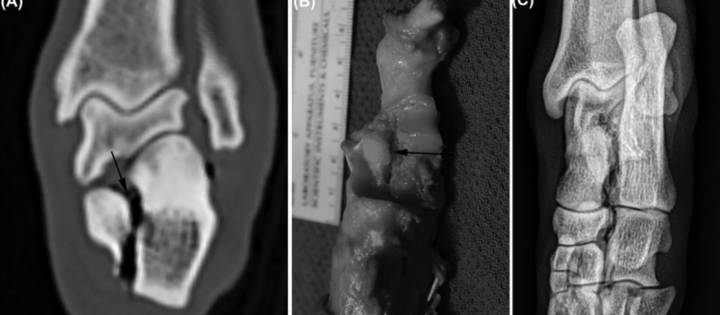

该数据集包含多个关节的骨折和非骨折 X 射线图像。任务是建立一个图像分类器来检测给定 X 射线图像中的骨折。该数据集由上肢的不同关节组成,建议隔离各个关节以增强分类器的性能。